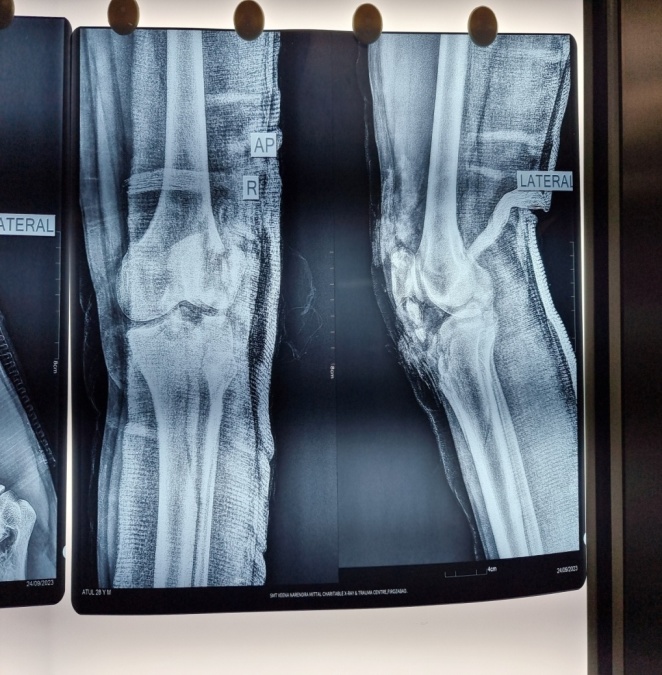

A 26 y-old male sustained a Type IIc Fraser and Type IVb Agarwal and Singh Floating knee injury on the right side. This included displaced intra-articular fractures of the lateral femoral condyle and lateral tibial plateau, a displaced patellar fracture with Grade II ACL tear and PCL sprain, complex tear of the lateral meniscus, and extensor mechanism rupture. Treatment involved external fixation for ipsilateral shaft fractures of the femur and tibia, along with a physiotherapy rehabilitation protocol for associated soft tissue injuries and tension band wiring for the patellar fracture. The patient achieved a good functional outcome after 2 y of follow-up, as depicted in [fig. 1a-d].

Fig. 1a: Preoperative X-ray AP and lateral view of 26 y old male having type IIc fraser and type IVb agarwal and singh floating knee injury